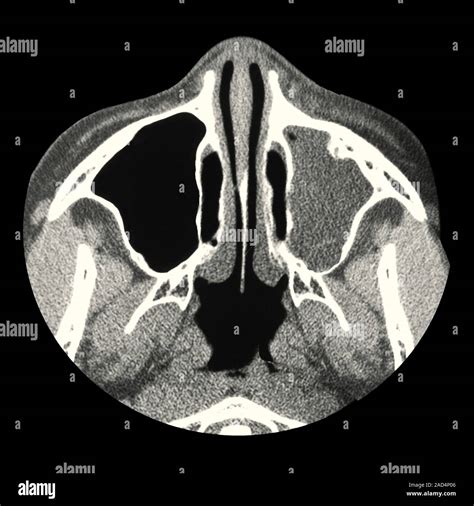

A Mxailliary Sinus CT scan, or Computed Tomography scan, is a non-invasive imaging procedure that uses X-rays to create detailed cross-sectional images of the sinuses. These images help doctors to identify abnormalities, infections, or structural issues within the sinuses. The scan is particularly useful for diagnosing conditions such as sinusitis, nasal polyps, and tumors.

The Mxailliary Sinus CT scan works by taking multiple X-ray images from different angles around the body. These images are then processed by a computer to create cross-sectional views of the sinuses. The resulting images provide a detailed view of the sinus cavities, allowing doctors to identify any abnormalities.

• Detailed Imaging: Provides high-resolution images of the sinuses, allowing for accurate diagnosis.